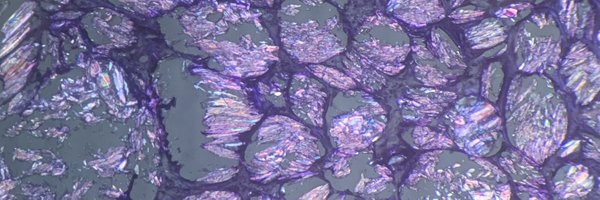

“Pen Test” confirming true psammoma body (PB) as opposed to thick colloid (or mucin). Gentle pressure on the cover slip with the tip of a pen while looking at the fragment under the scope will radially fracture a true PB (Thyroid, FNA, PTC). Same fragment, before/after the test.

14

56

210